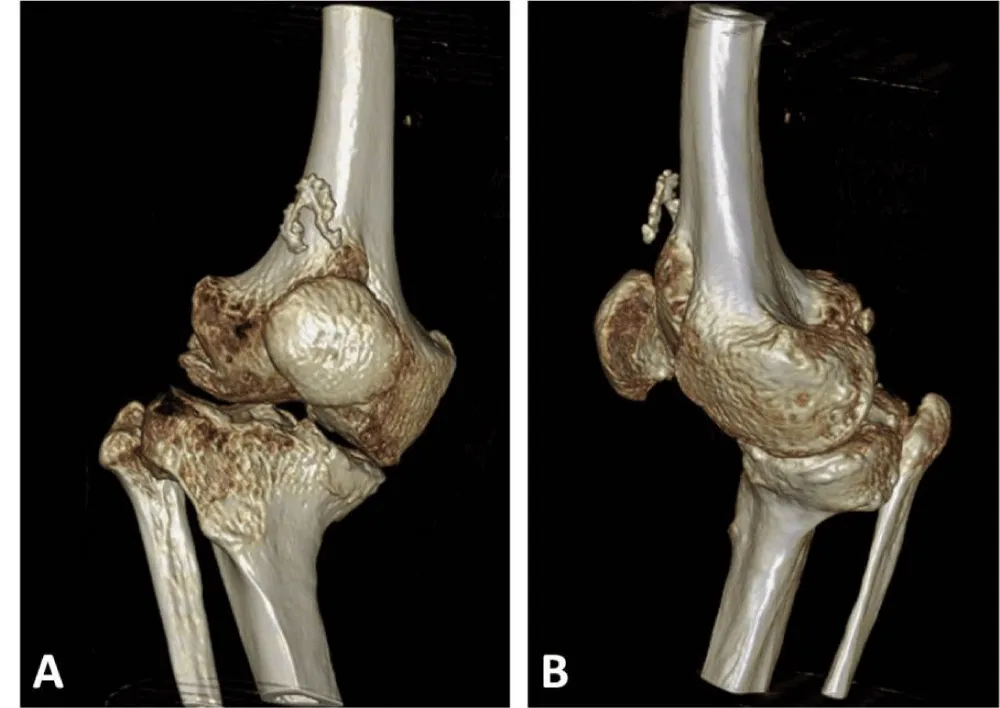

X-rays reveal severe deforming osteoarthritis of the right knee with a medial tibial metaphyseal angle of 53.6° (Figure 1). Telemetry shows medialization of the weight-bearing axis of the right lower extremity due to severe genu varum (Figure 2). Computed tomography (CT) confirms joint destruction with varus deformity of the proximal tibia (Figure 3), and severe misalignment of the posterior tibial slope (Figure 4).

There are several surgical options for addressing knee deformities in patients with achondroplasia, including TKA without correcting mild deformities or correcting significant misalignments in one or two stages. Varus alignment of the knee can be caused by tibial deformities, combined tibiofemoral deformities, or ligament imbalances. Understanding the malalignment is essential in TKA to restore the neutral mechanical axis in the frontal plane. The most common knee morphotype in achondroplasia patients is genu varum with widened metaphyses. Occasionally, extra-articular metaphyseal varus angulation may be linked to lateral collateral ligament insufficiency and flexion contractures, which can restrict range of motion. Therefore, technical challenges in TKA for these patients include soft tissue contractures, ligament laxity, extra-articular deformities, and difficulties with standard prosthesis sizing due to bone size and joint structural abnormalities. It is widely agreed that CT scans are crucial for preoperative planning in these cases, helping assess bone mass, deformities, and implant sizes to ensure proper prosthetic component fit in the femur and tibia medullary canals. Custom implants are often necessary in cases of skeletal dysplasia.